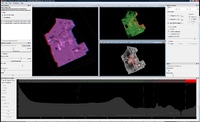

A screenshot of ImageVis3D, demonstrating the ClearView [1] feature on the visible human male dataset. | |

ImageVis3D is a lightweight, open source, volume rendering application for the interactive visualization of very large volumetric data sets. It utilizes both the slice based as well as the GPU ray casting approach to visualize the volume data. The source code is currently maintained in a publicly accessible Subversion repository [2] by the Scientific Computing and Imaging Institute [3] at the University of Utah.

- supports 1D and 2D transfer functions as well as isosurface extraction and the ClearView rendering technique

ImageVis3D rendering the engine volume data set in different modes. |